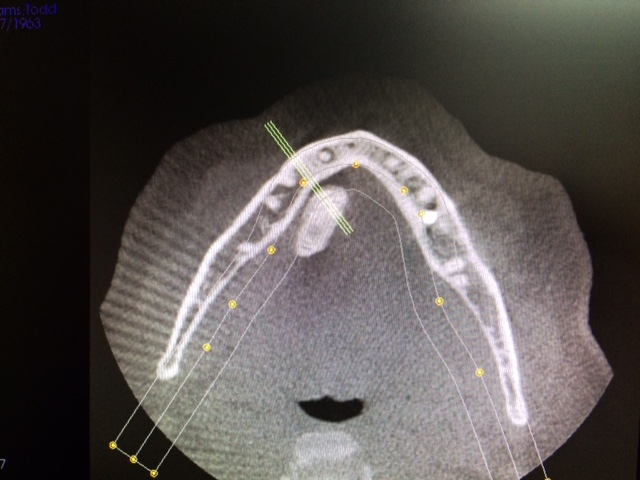

Head and Neck Tumor and Reconstruction

(cancer reconstruction)

Often after a patient has gone through various treatments for cancer there is a need that oral and maxillofacial services can provide for. In many cases, reconstructive surgery benefits patients having gone through specific skin cancers that are typically found in and around the head and neck regions. Depending on the severity and location of the cancer, skin cancer reconstruction options can range from simple to advanced procedures in order to restore both function and form.

The photos on this website are from real surgeries performed by Dr. Ulloa. Due to the

graphic nature of the images and content, viewer discretion is advised.